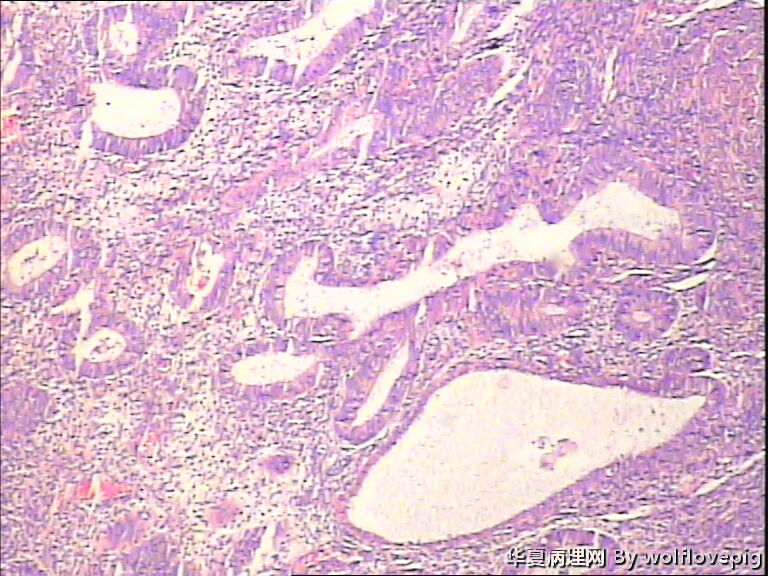

求助,子宫内膜!

48y

子宫内膜复杂性非典型增生(有没有癌变,待制作优良的切片再诊断吧)。

复杂性非典型增生

复杂性非典型增生(EIN)

子宫内膜复杂性非典型增生